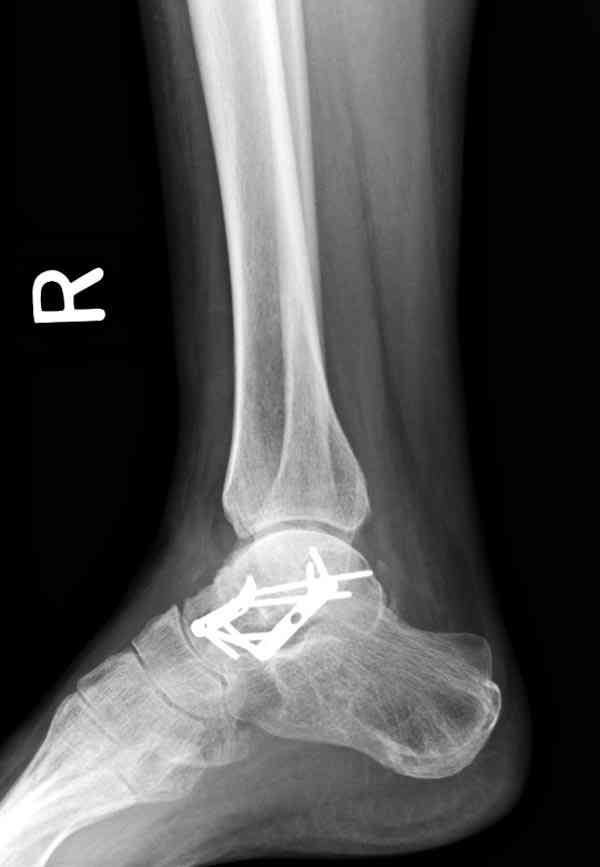

Решили не связываться с остеосинтезом, а сделать сразу берцово-пяточный блок. Снимки в приложении.

По завершении удлинения, наверно, заштифтуем.

Комментарии/критика приветствуются.